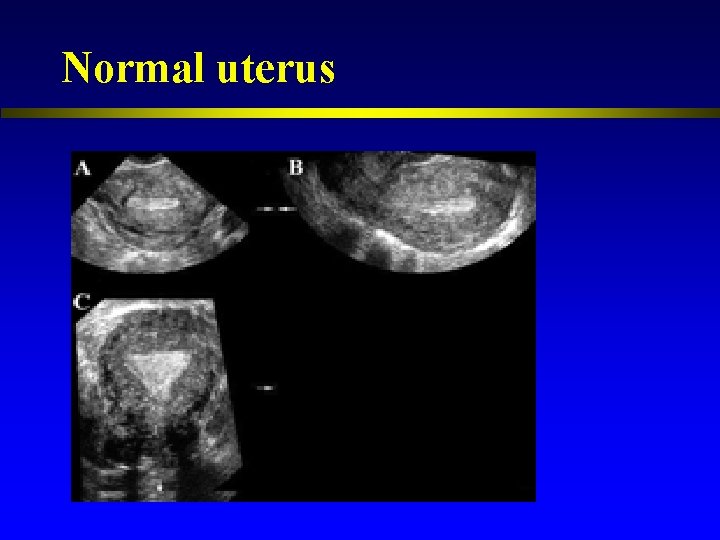

Normal uterus